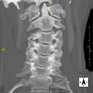

- TC Columna cervical Prueba radiológica que consiste en obtener imágenes de las vertebras cervicales de alta definición anatómica mediante el empleo de un equipo de TC (Tomografía Computarizada). Indicaciones: cervicalgia sin/con irradiación a brazos, traumatismo. Prueba radiológica que consiste en obtener imágenes de las vertebras cervicales de alta definición anatómica mediante el empleo de un equipo de TC (Tomografía Computarizada). Indicaciones: cervicalgia sin/con irradiación a brazos, traumatismo.

- Columna- TC Columna cervical Prova radiològica que consisteix en obtenir imatges de les vèrtebres cervicals d'alta definició anatòmica, mitjançant l'ús d'un equip de TC (Tomografia Computeritzada). Indicacions: dolor cervical amb/sense irradiació als braços, traumatisme, malformacions congènites. Prova radiològica que consisteix en obtenir imatges de les vèrtebres cervicals d'alta definició anatòmica, mitjançant l'ús d'un equip de TC (Tomografia Computeritzada). Indicacions: dolor cervical amb/sense irradiació als braços, traumatisme, malformacions congènites.